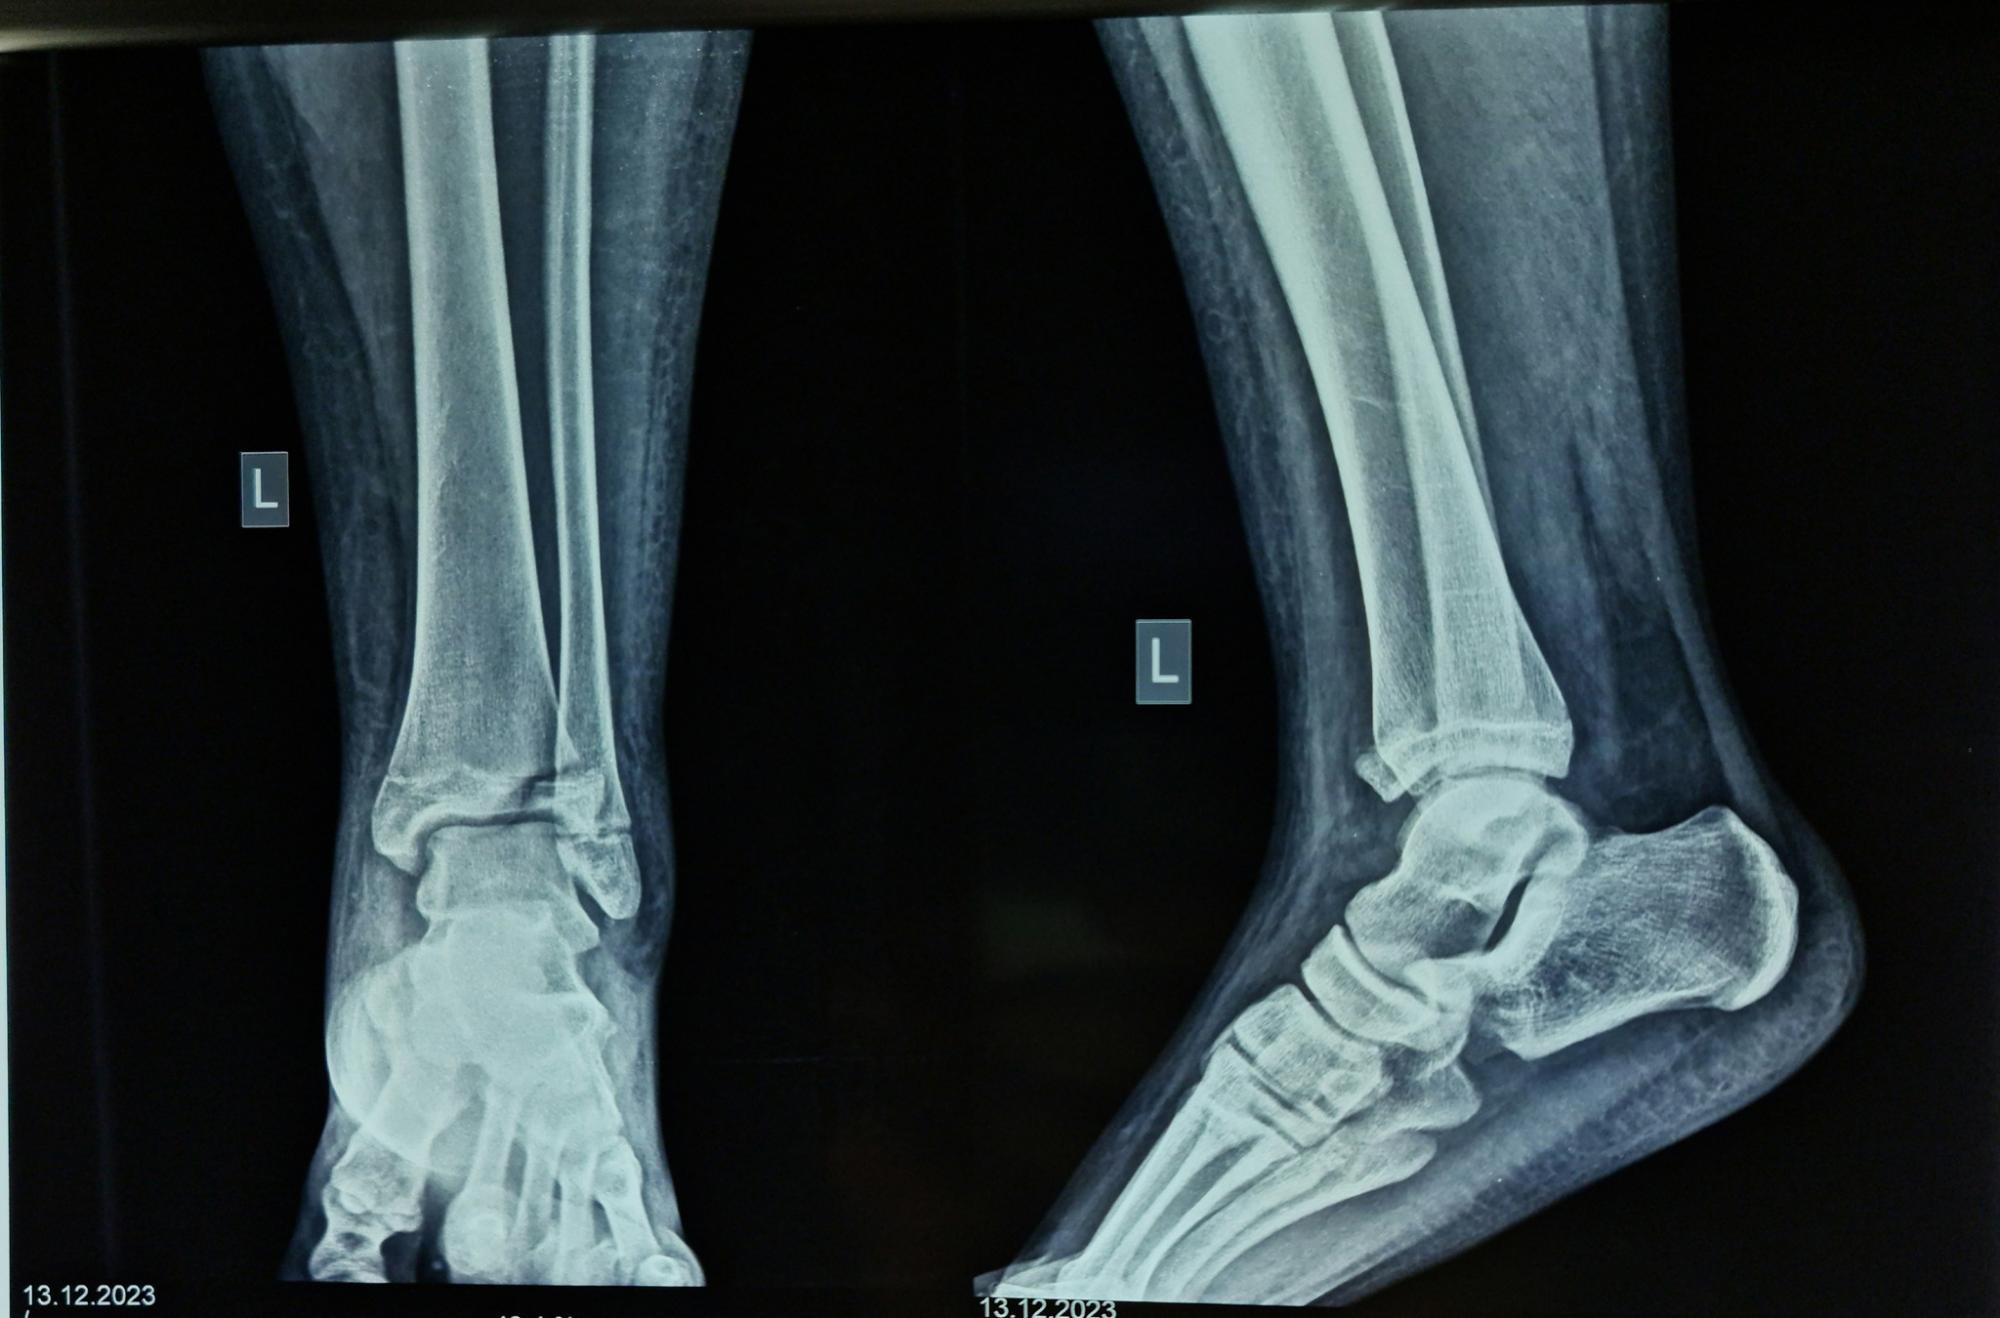

Как выглядит нога после операции (фото: facebook.com/RivneODL)

Пациентку госпитализировали в ортопедо-травматологический центр больницы с переломом большеберцовой кости, которому было уже две недели. С помощью рентгенографии удалось определить, что это был редкий перелом Тилло.

Отмечается, что для лечения перелома Тилло используется методика открытой репозиции и фиксации титановым винтом. После операции полное восстановление функции голеностопного сустава занимает от 6 до 12 месяцев.